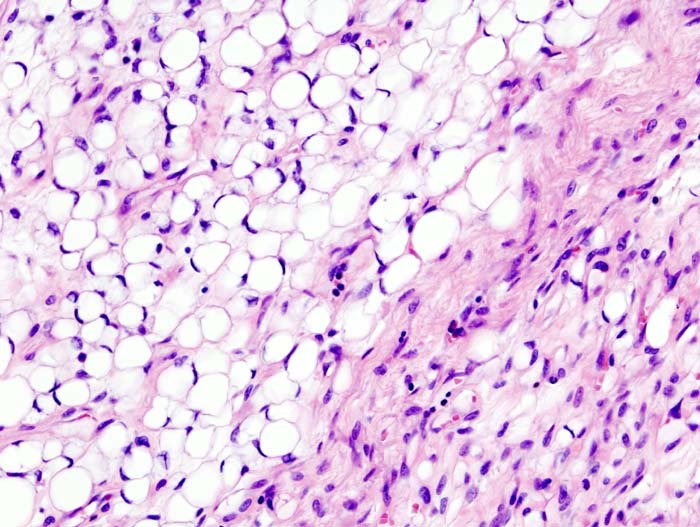

Liposarcoma

Liposarcomas are malignant tumors of adipose tissue.

Liposarcomas are very rare compared to lipomas (their benign counterparts).

Liposarcomas may metastasize.

Adults are more commonly susceptible to developing liposarcomas compared to children.

Definitive diagnosis of liposarcoma is made by pathology showing malignant proliferation of adipose tissue.

Lipoblasts are the characteristic cells seen in liposarcoma.

Treatment of liposarcomas involves surgical excision.